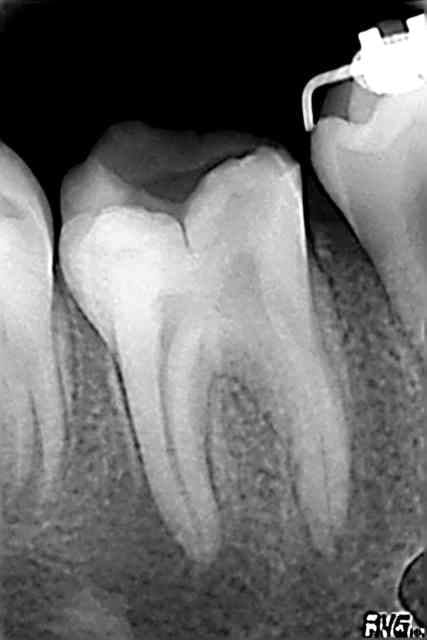

Et deux mois apres, voila ma Marie qui revient. Avec un joli bourgeon sur la gencive entre 46 et 45. No Dolor.

Je plante mon gros cône de gutta dedans, et voilà la radio 03 (celle de gauche).

keskonfé ? Une RTE ? Ferais-je mieux ? Resection apicale ? Un scan (mais faut tout débracketter)... ?